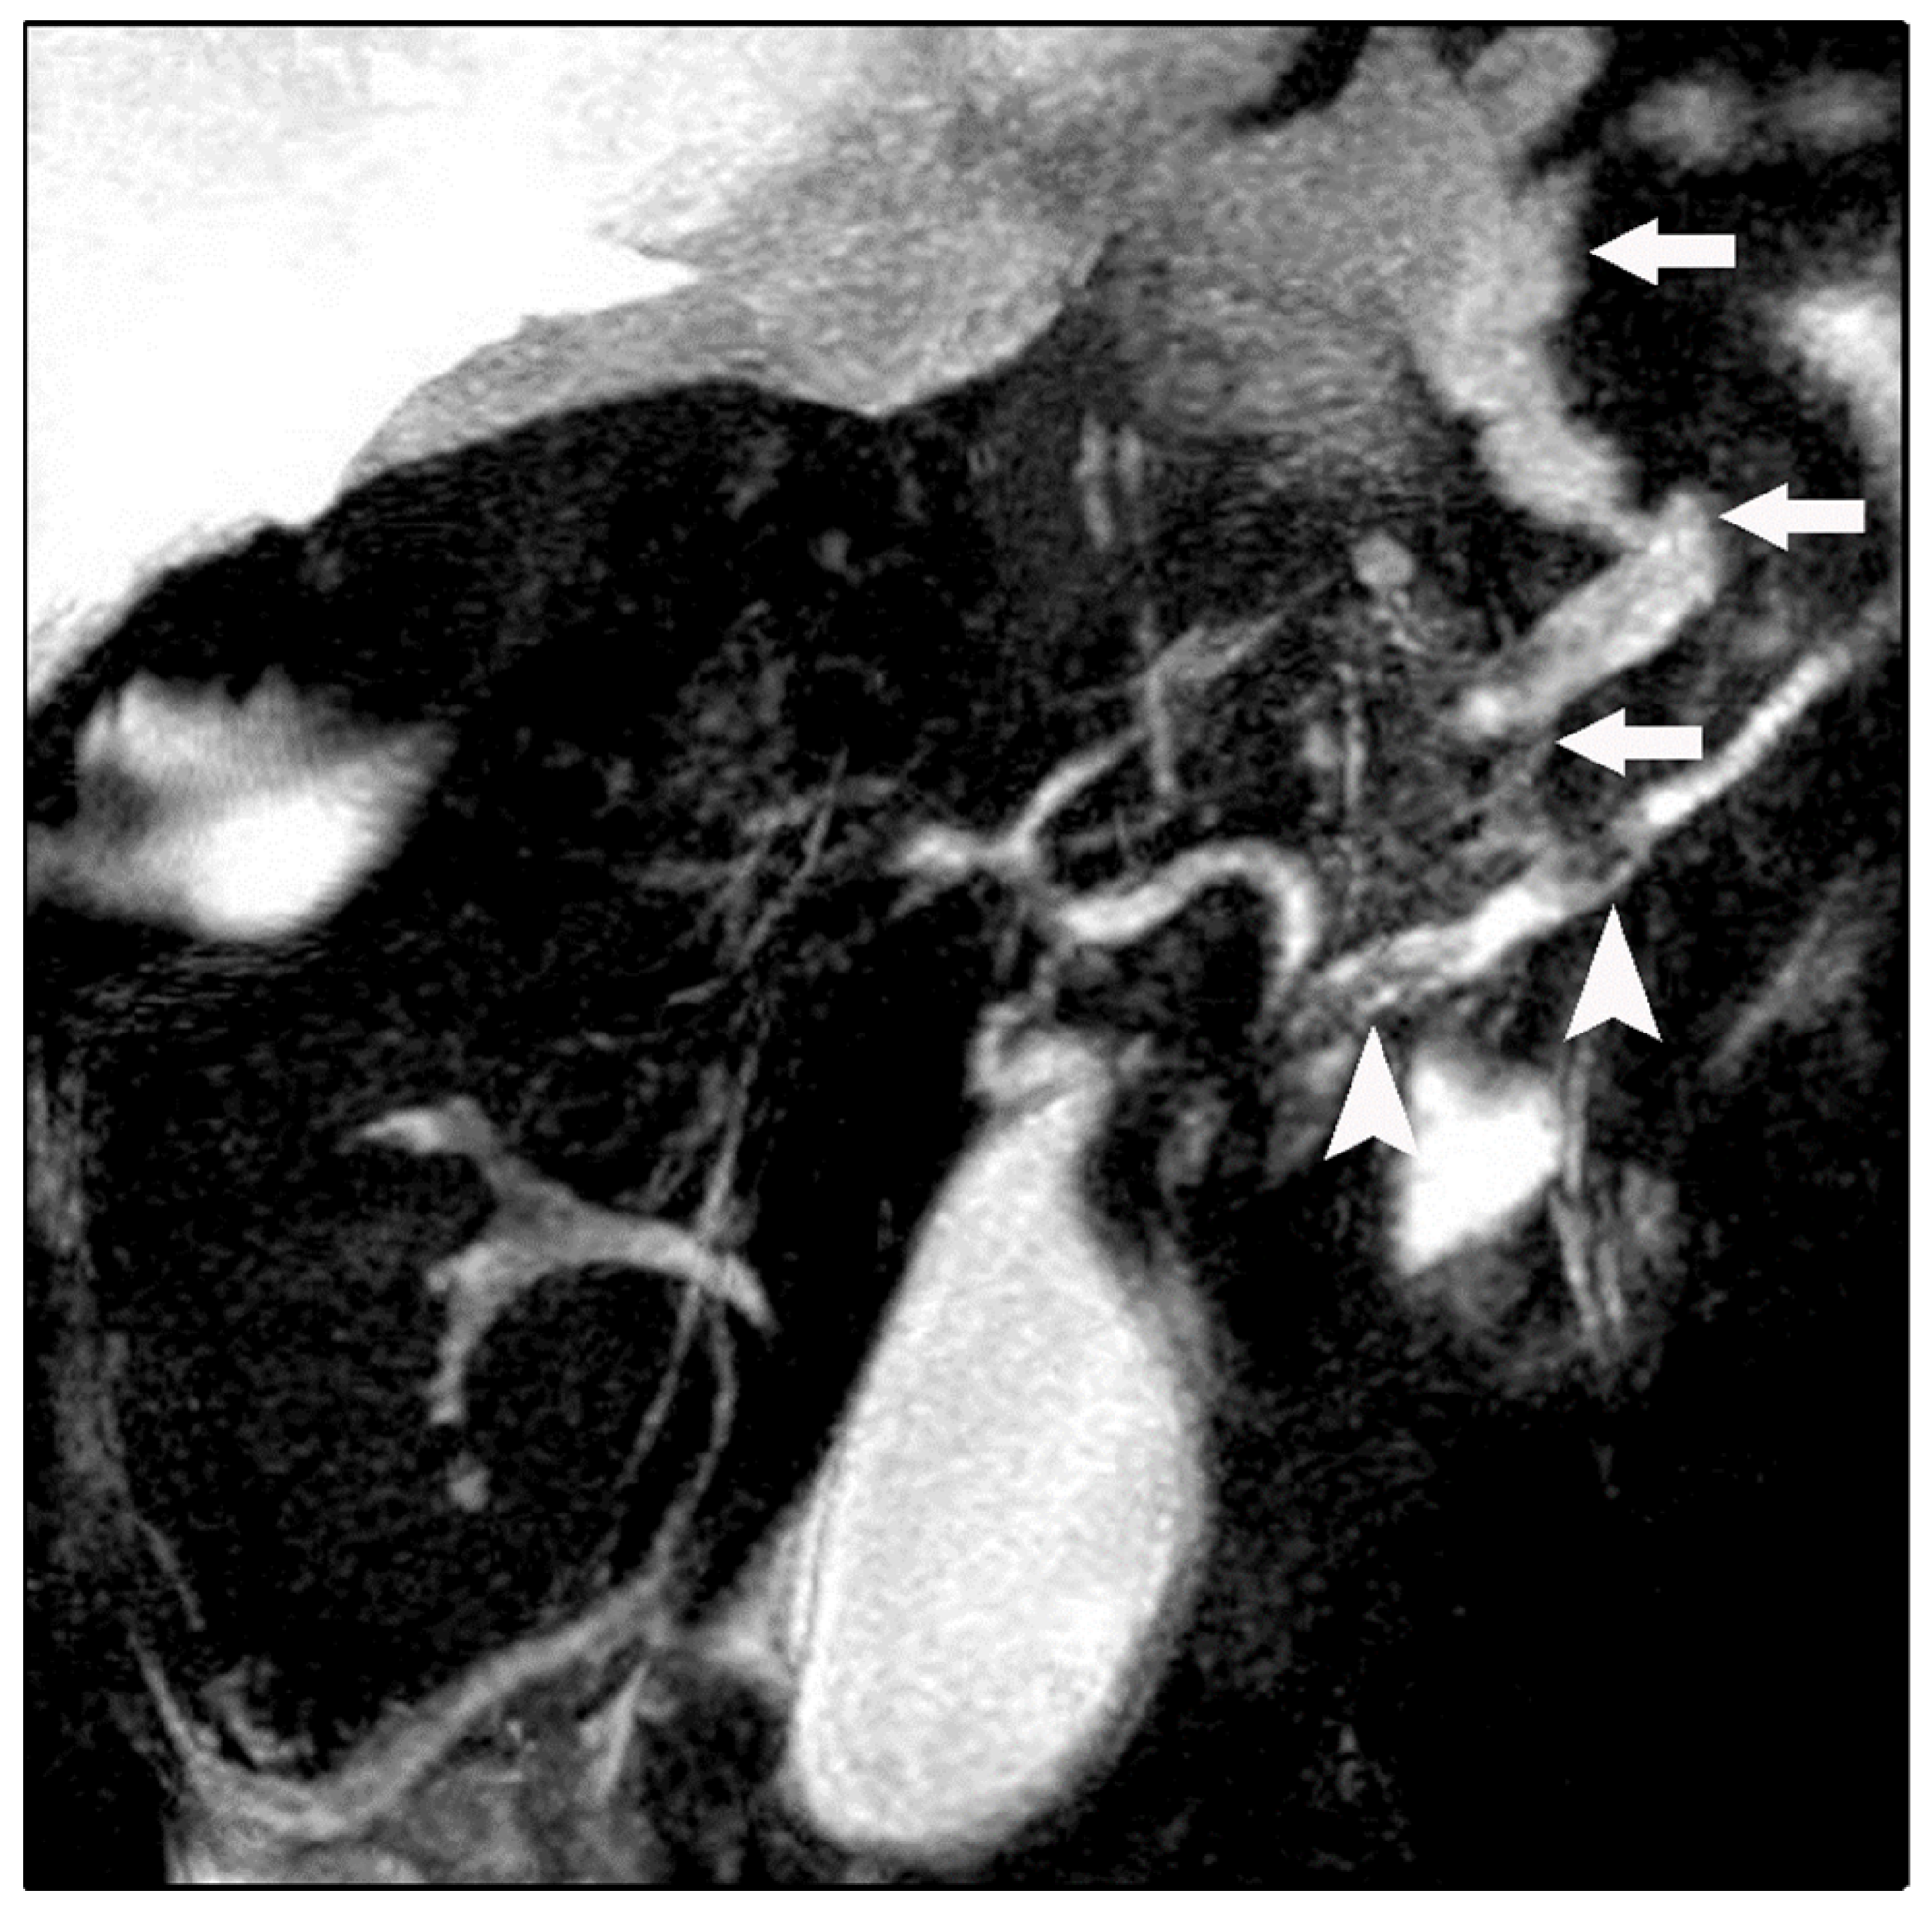

Chest radiography revealed bilateral pleural effusions, more pronounced on the right side (Figure 1). Contrast-enhanced thoracoabdominal computed tomography (CT) confirmed bilateral pleural effusions with associated ascites (Figure 2). The pancreas appeared atrophic with dilatation of the main pancreatic duct, consistent with chronic pancreatitis. A peripancreatic fluid collection extended toward the esophageal hiatus, coursing into the mediastinum and pleural spaces. Magnetic resonance imaging (MRI) confirmed pancreatic atrophy, while magnetic resonance cholangiopancreatography demonstrated an irregularly dilated main pancreatic duct measuring approximately 1 cm with intraductal filling defects. A fistulous tract originating from the pancreatic body and extending through the left side of the esophageal hiatus into the mediastinum was identified. The biliary tree and gallbladder were unremarkable, and no further pancreatic lesions were appreciated (Figure 3), thus not necessitating further evaluation with EUS. These findings established the diagnosis of chronic calculous pancreatitis complicated by a pancreaticopleural fistula. As imaging studies took place promptly following initial presentation, and the suspicion of pancreaticopleural fistula was established early, pleural fluid amylase levels were not sent for this patient.

Figure 3.

Magnetic resonance cholangiopancreatography (MRCP) revealing a fistulous fluid tract arising from a disruption of the main pancreatic duct and coursing toward the esophageal hiatus (arrows). Intraductal filling defects consistent with pancreatic duct calculi are also noted (arrowheads).

Imaging plays a central role in establishing the diagnosis of pancreaticopleural fistula. While computed tomography is useful for identifying pancreatic morphology, ductal dilatation, and associated fluid collections, it may fail to delineate the fistulous tract in a significant proportion of cases [21,22,23]. In our patient, CT imaging was instrumental in demonstrating mediastinal and pleural fluid extension but did not fully define the fistulous communication. Magnetic resonance cholangiopancreatography (MRCP) has emerged as the preferred noninvasive imaging modality, offering superior visualization of the pancreatic ductal anatomy and fistulous communication without the risks associated with invasive procedures [24,25]. MRCP in this case clearly demonstrated both the fistulous tract and intraductal calculi, directly influencing therapeutic decision-making. Endoscopic retrograde cholangiopancreatography (ERCP), although historically considered the diagnostic gold standard, is now primarily reserved for therapeutic intervention due to its invasiveness and risk of procedure-related pancreatitis [26].